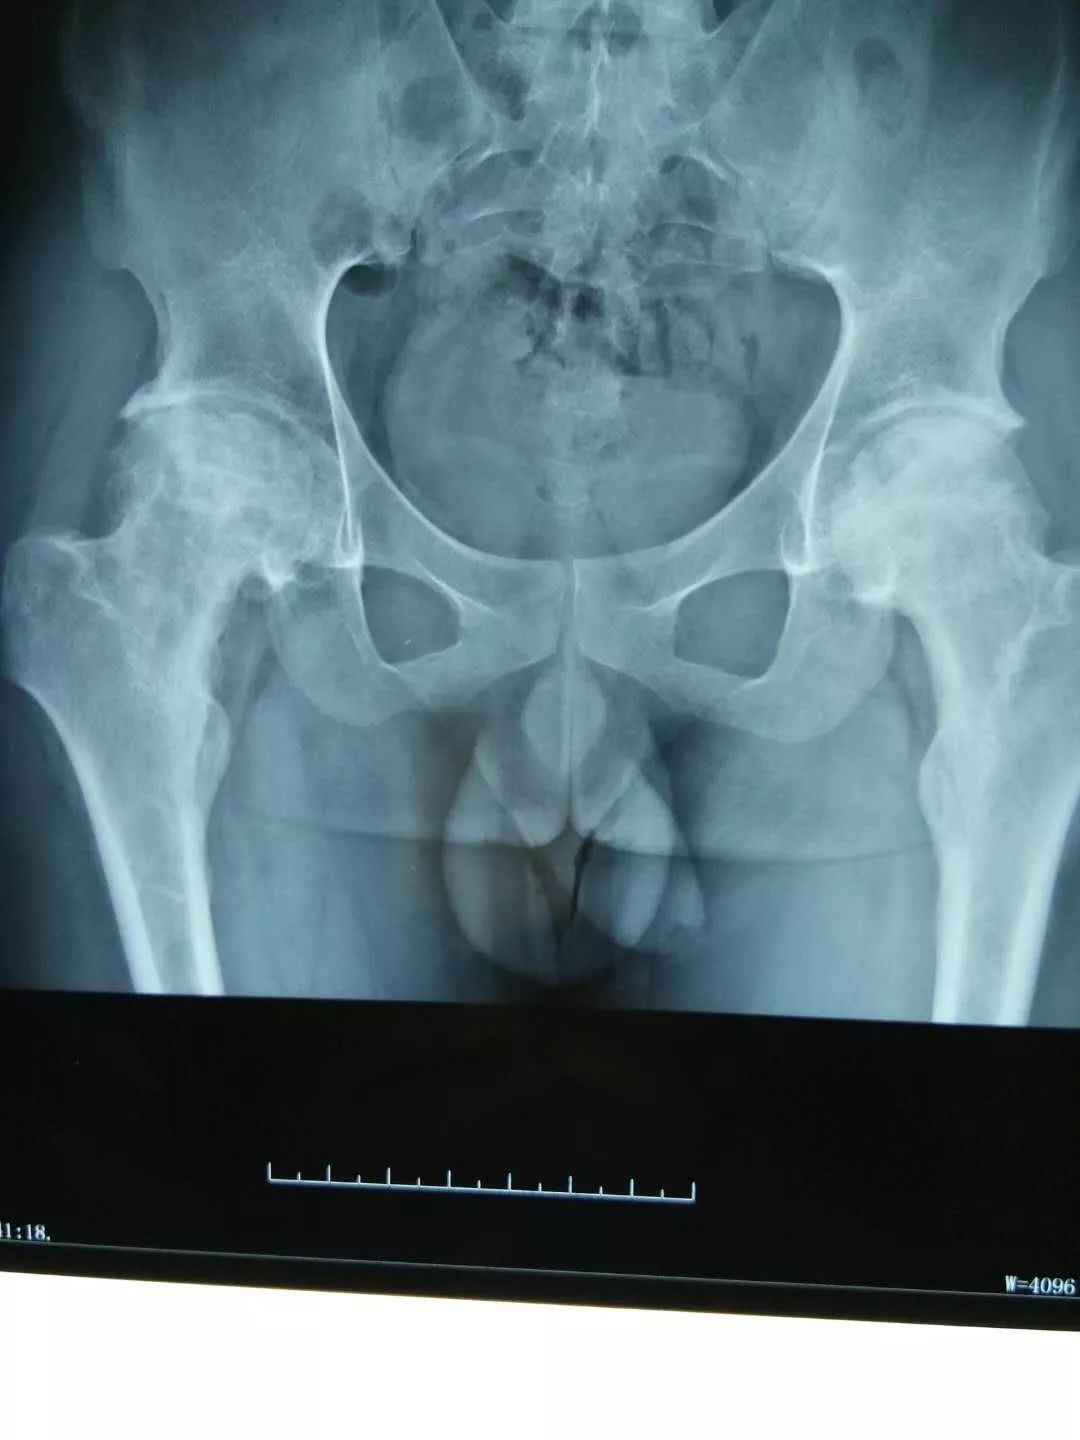

一名*安泰**的女性股骨头坏死患者,在儿女强力怂恿下来淄博找廉从希求医,一开始对“廉氏三联疗法”并不抱太大信心,但一个疗程结束后,患者便惊喜地发来医院检查的骨片,股骨头坏死部位纹理已明显开始致密均匀,病情有了很大好转。患者自此坚定了治疗信心,持续治疗3个月后痊愈。

经对118名患者跟踪调查,“廉氏三联疗法”对股骨头坏死的总有效率在92%以上;显效率(症状明显好转,功能障碍恢复)87%以上;病理改善率(影像显示骨密度增强)83%以上;临床治愈率(观察一年以上,症状消失,功能障碍恢复,可做日常家务及轻体力劳动)75%。

左图为治疗前,右图为治疗后。